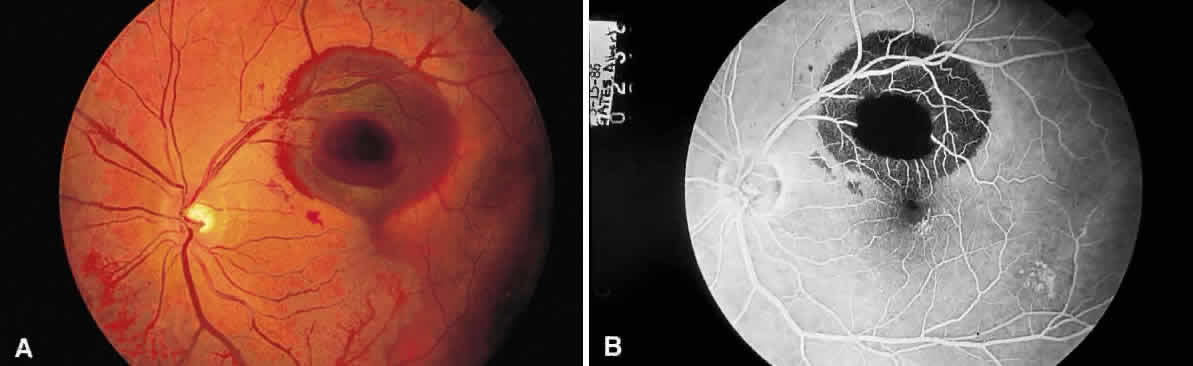

Fig. 16. Fundus photograph of a disciform macular scar, white because of fibrosis and atrophy of the pigment epithelium. A broad, C-shaped, fresh hemorrhage within the sensory retina surrounds it.

Fibrous tissue may originate from the choroid and proliferate through breaks in Bruch's membrane into the subpigment epithelial or subretinal spaces,4 hence the white appearance of disciform macular degeneration (Fig. 16). Fibrous tissue also may originate from fibroblasts located in the adventitia of retinal vessels and may contribute to the white appearance of vascularized membranes (Fig. 17A), such as those seen in proliferative diabetic retinopathy (see Fig. 17B) or arterioles after vascular occlusion (see Fig. 6). The accretion of collagen in the wall of the vessel in arteriolosclerosis may thicken the vessel wall (see Fig. 5) and alter the color of the blood column to a copper or silver color. Injury to the pigment epithelium results in scar formation (Fig. 18). Collagen deposition from pigment epithelium metaplasia may be identified by the presence of pigment within a scar (Fig. 19). Injured nonpigmented epithelium may undergo similar fibrous metaplasia and may contribute to the formation of membranes such as cyclitic membranes in the region of the ciliary body.